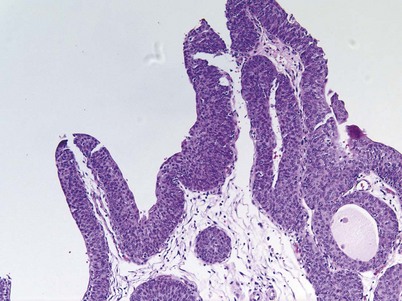

Cystitis cystica and/or glandularis is a common finding in normal bladders, usually associated with inflammation or chronic obstruction (Semins and Schoenberg, 2007). These benign tumors represent cystic nests that are lined by columnar or cuboidal cells and are generally associated with proliferation of Von Brunn nests (Figs. 80-3 and 80-4). Cystitis glandularis can be associated with pelvic lipomatosis and may occupy the majority of the bladder (Buckley et al, 2007). Cystitis glandularis may develop into or coexist with intestinal metaplasia, which are benign tumors characterized by goblet cells that are histologically similar to colonic epithelium. There have been a few case reports of cystitis cystica or glandularis transforming into adenocarcinoma, and therefore regular endoscopic evaluation of patients with these entities is recommended (Smith et al, 2008). The most common presenting feature of cystitis cystica or glandularis is irritative voiding symptoms and hematuria. Treatment is transurethral resection and relief of the obstruction or inflammatory condition.